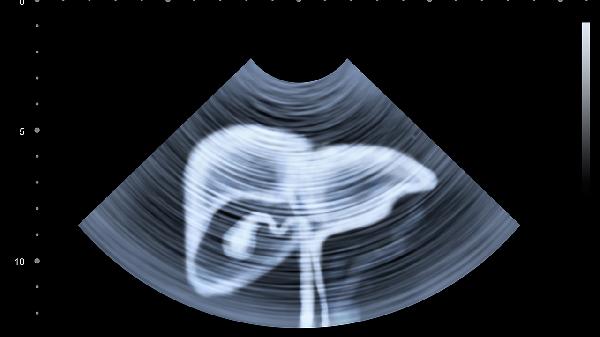

建议肝脏切除术后保持高蛋白、高维生素饮食,适量补充支链氨基酸。避免饮酒和使用肝毒性药物,定期复查超声和肝功能。如出现持续乏力、黄疸或腹水应及时就医。对于肝硬化患者,需终身随访监测再生情况及肝癌复发风险。